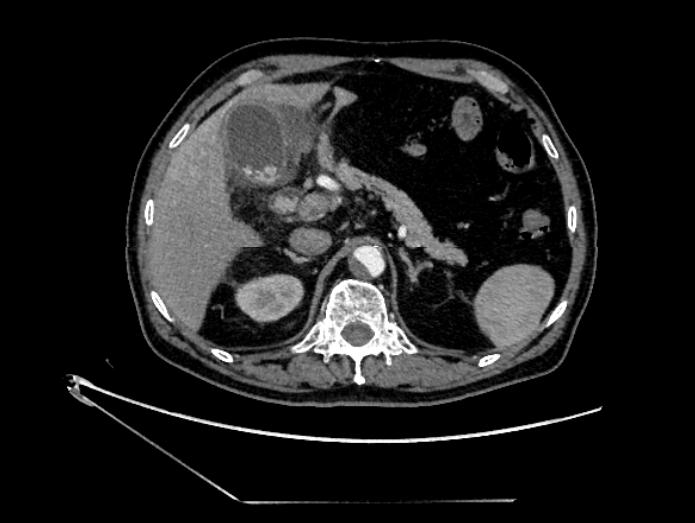

经过详细询问病史了解到,潘大爷胆囊结石病史已有多年,但未发作如此厉害!入院后急查了上腹部CT,果不其然,潘大爷的胆管明显扩张,胆囊及胆管均遍布大小不一的结石。此外,潘大爷十几年前曾因消化道穿孔行毕II式胃大切手术,他的消化道结构已与正常人不同。此外,他还伴有心脏早搏、高血压、脑梗塞等病史,血压平时控制得也不是很理想,使得家属十分忧虑。

图1:上腹部CT提示:胆囊及胆总管多发结石并感染